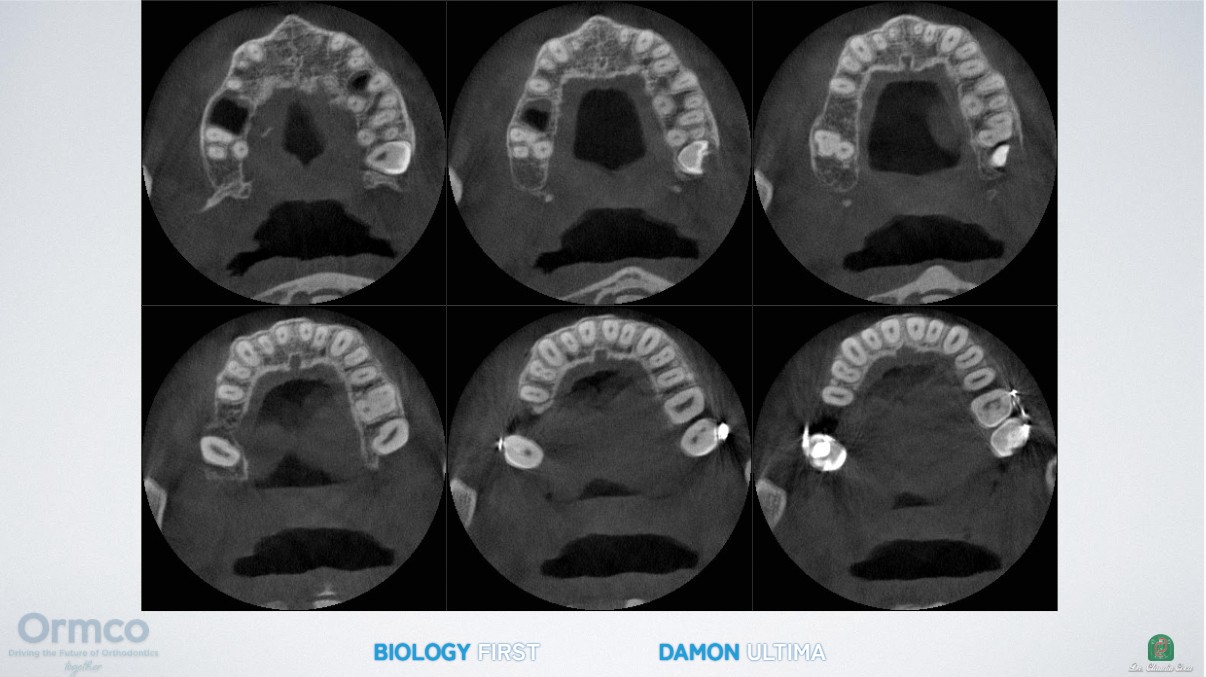

Orthodontic tooth movement is fundamentally a process of alveolar bone remodeling driven by low-force, low-friction biomechanics (pressure-tension theory: osteoclast activity on the pressure side and osteoblast activity on the tension side).¹

The Damon Ultima passive self-ligating system, used properly with actual low forces, allows teeth to move through bone in a more physiological manner without the need for heavy mechanics. At the same time, the functional matrix of the masticatory muscles is respected.

Through this Biology First approach, excellent clinical results are achieved while substantially reducing the need for more invasive interventions such as rapid palatal expansion (RPE), dental extractions, interproximal stripping (IPR), and orthognathic surgery. This minimally invasive strategy helps preserve natural muscle balance and function, leading to improved long-term stability, TMJ health, and more harmonious facial aesthetics.

Patient-Specific Archform Generated by Function

A distinctive feature of the Damon Philosophy is that the final archform is unique to each patient—it is generated by function and the patient’s own biology rather than being decided by mathematical formulas (as in classical orthodontics) or by tooth-driven mechanics (as in aligners).